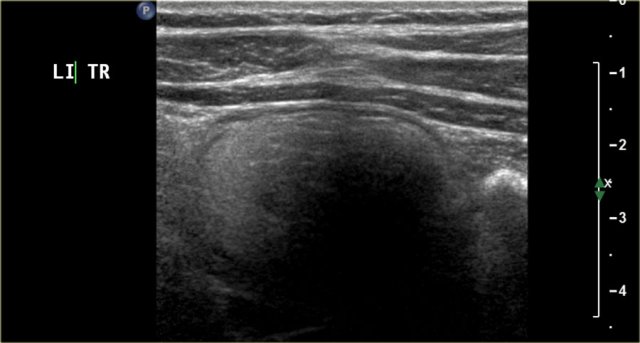

The image is of a one-month-old boy with a MCKD on prenatal ultrasound.

Some tissue and several large cysts are seen.

On Tc-99-DMSA scintigraphy no uptake was seen on the left side.

This is compatible with a MCKD.